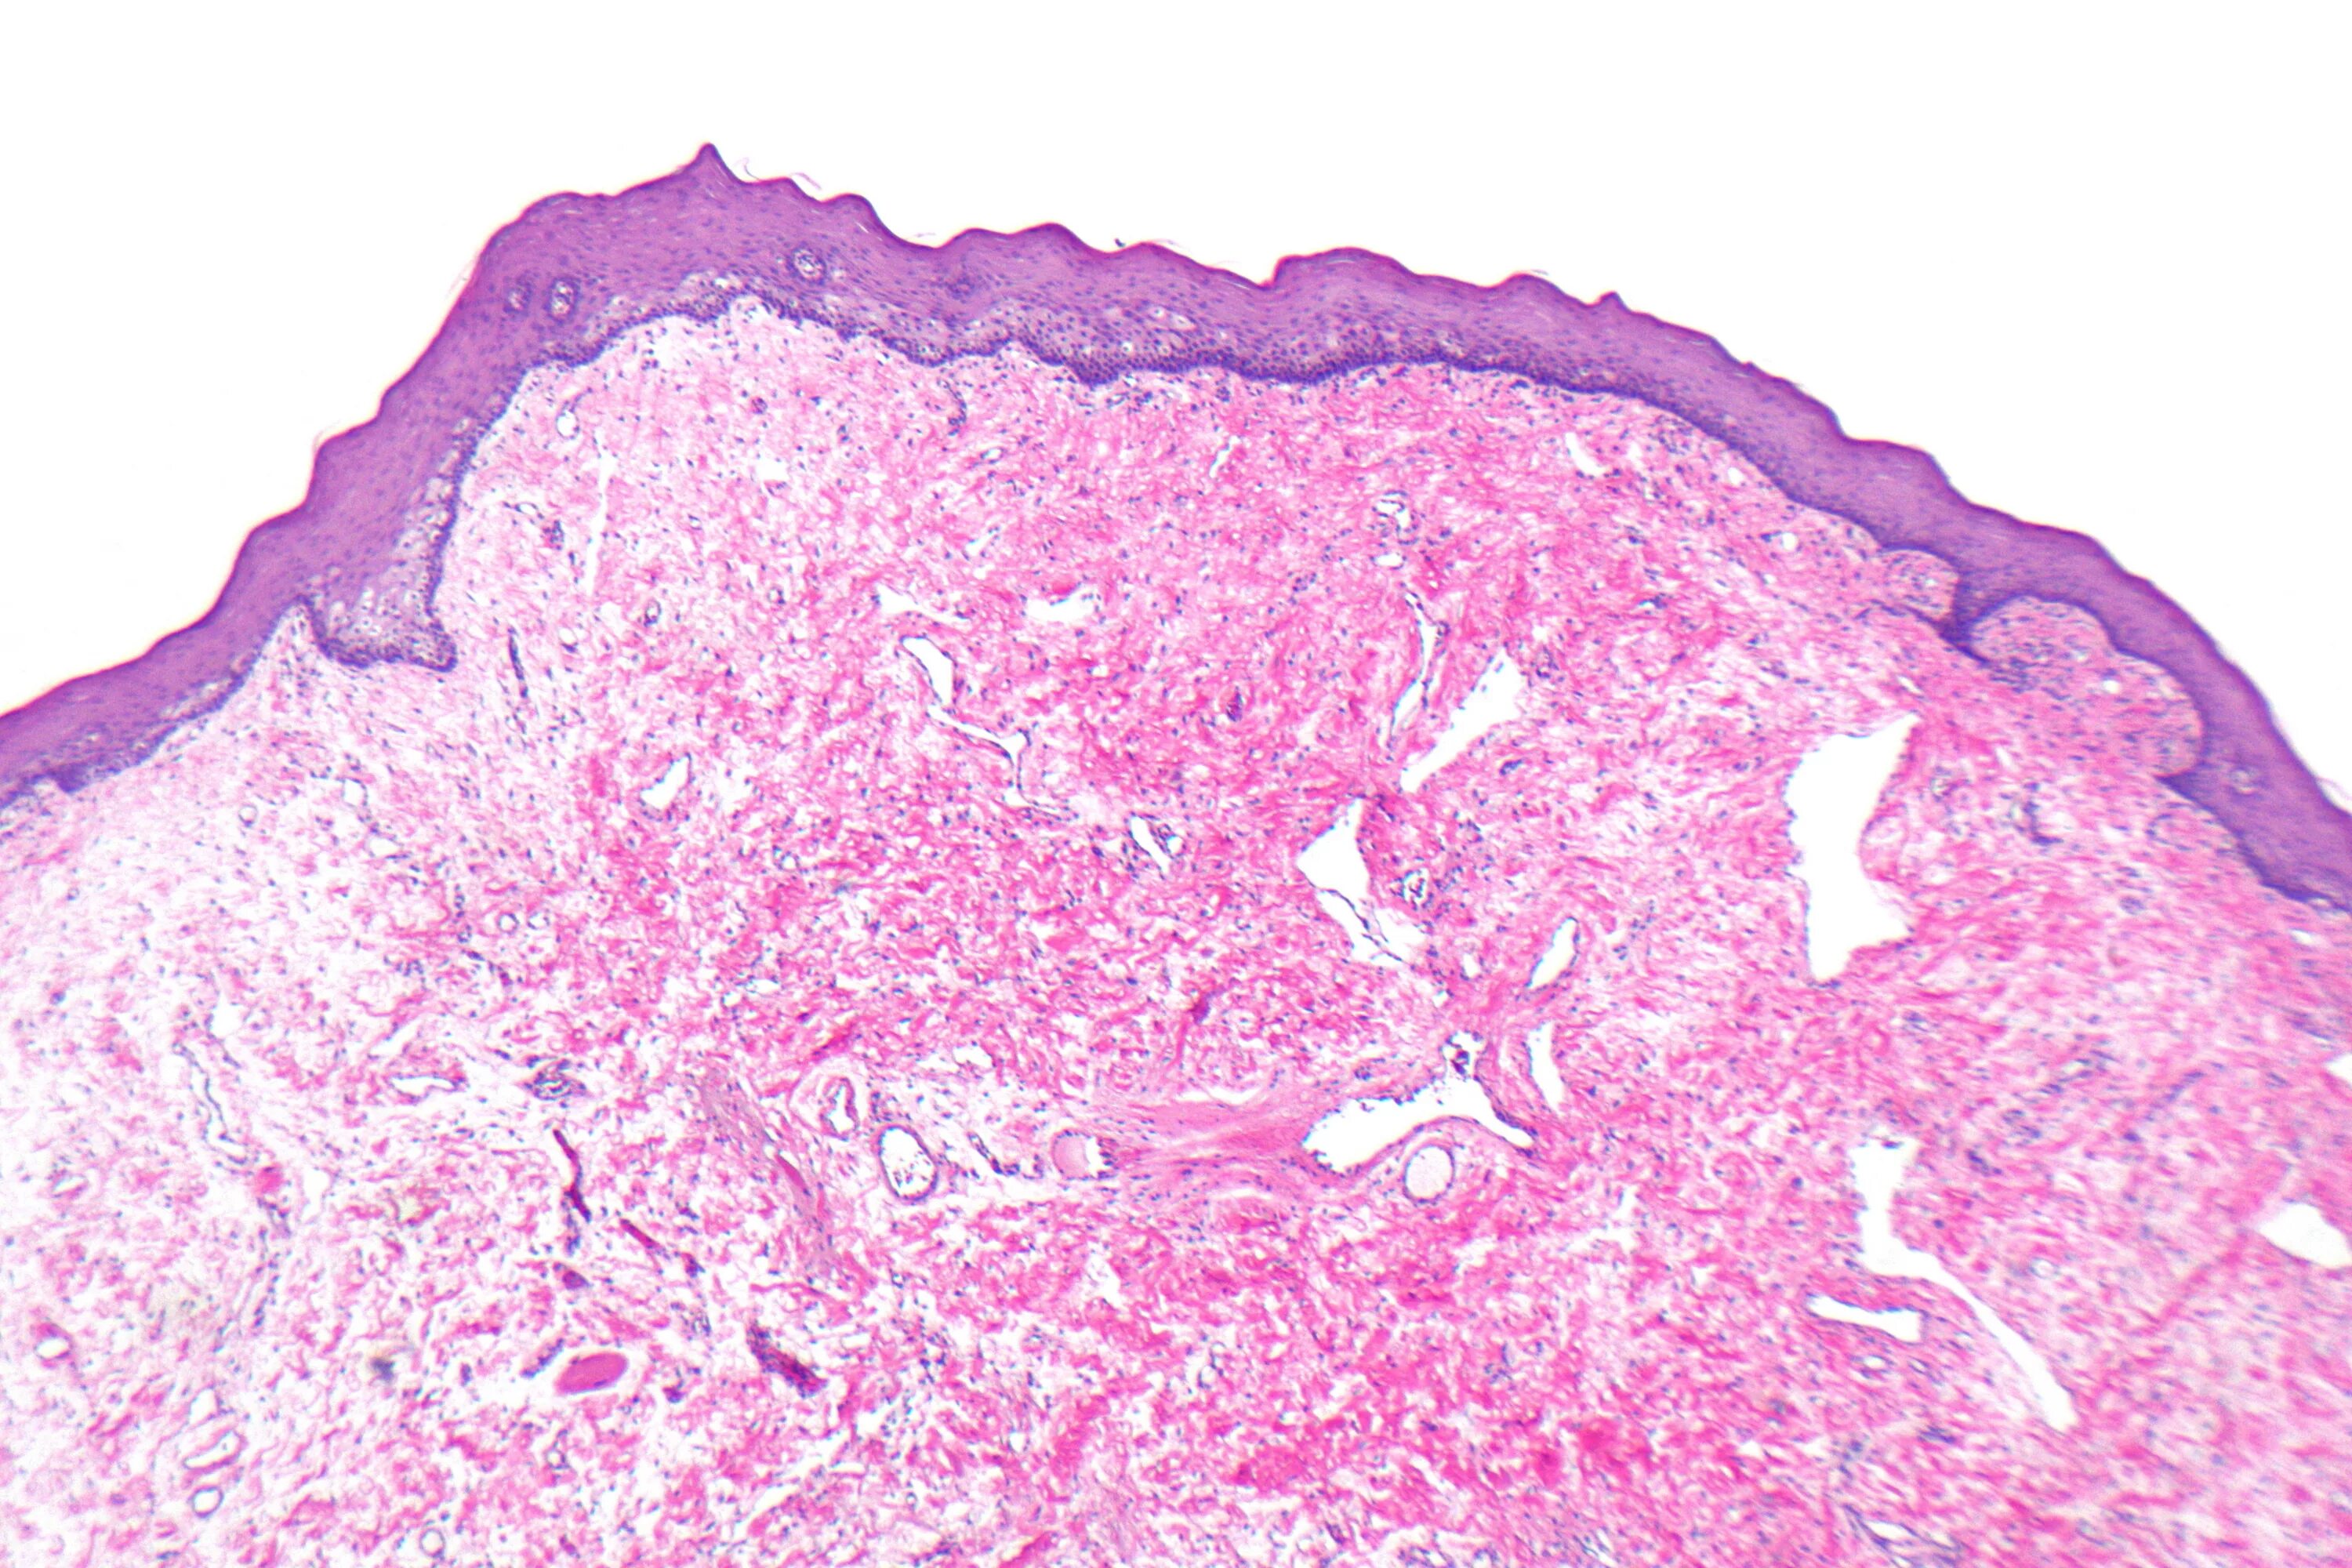

Фиброматоз мягких